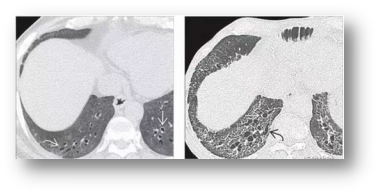

4、呼吸系統(tǒng)表現(xiàn)

漸進(jìn)性勞力性呼吸困難、活動(dòng)后氣短、干咳等。